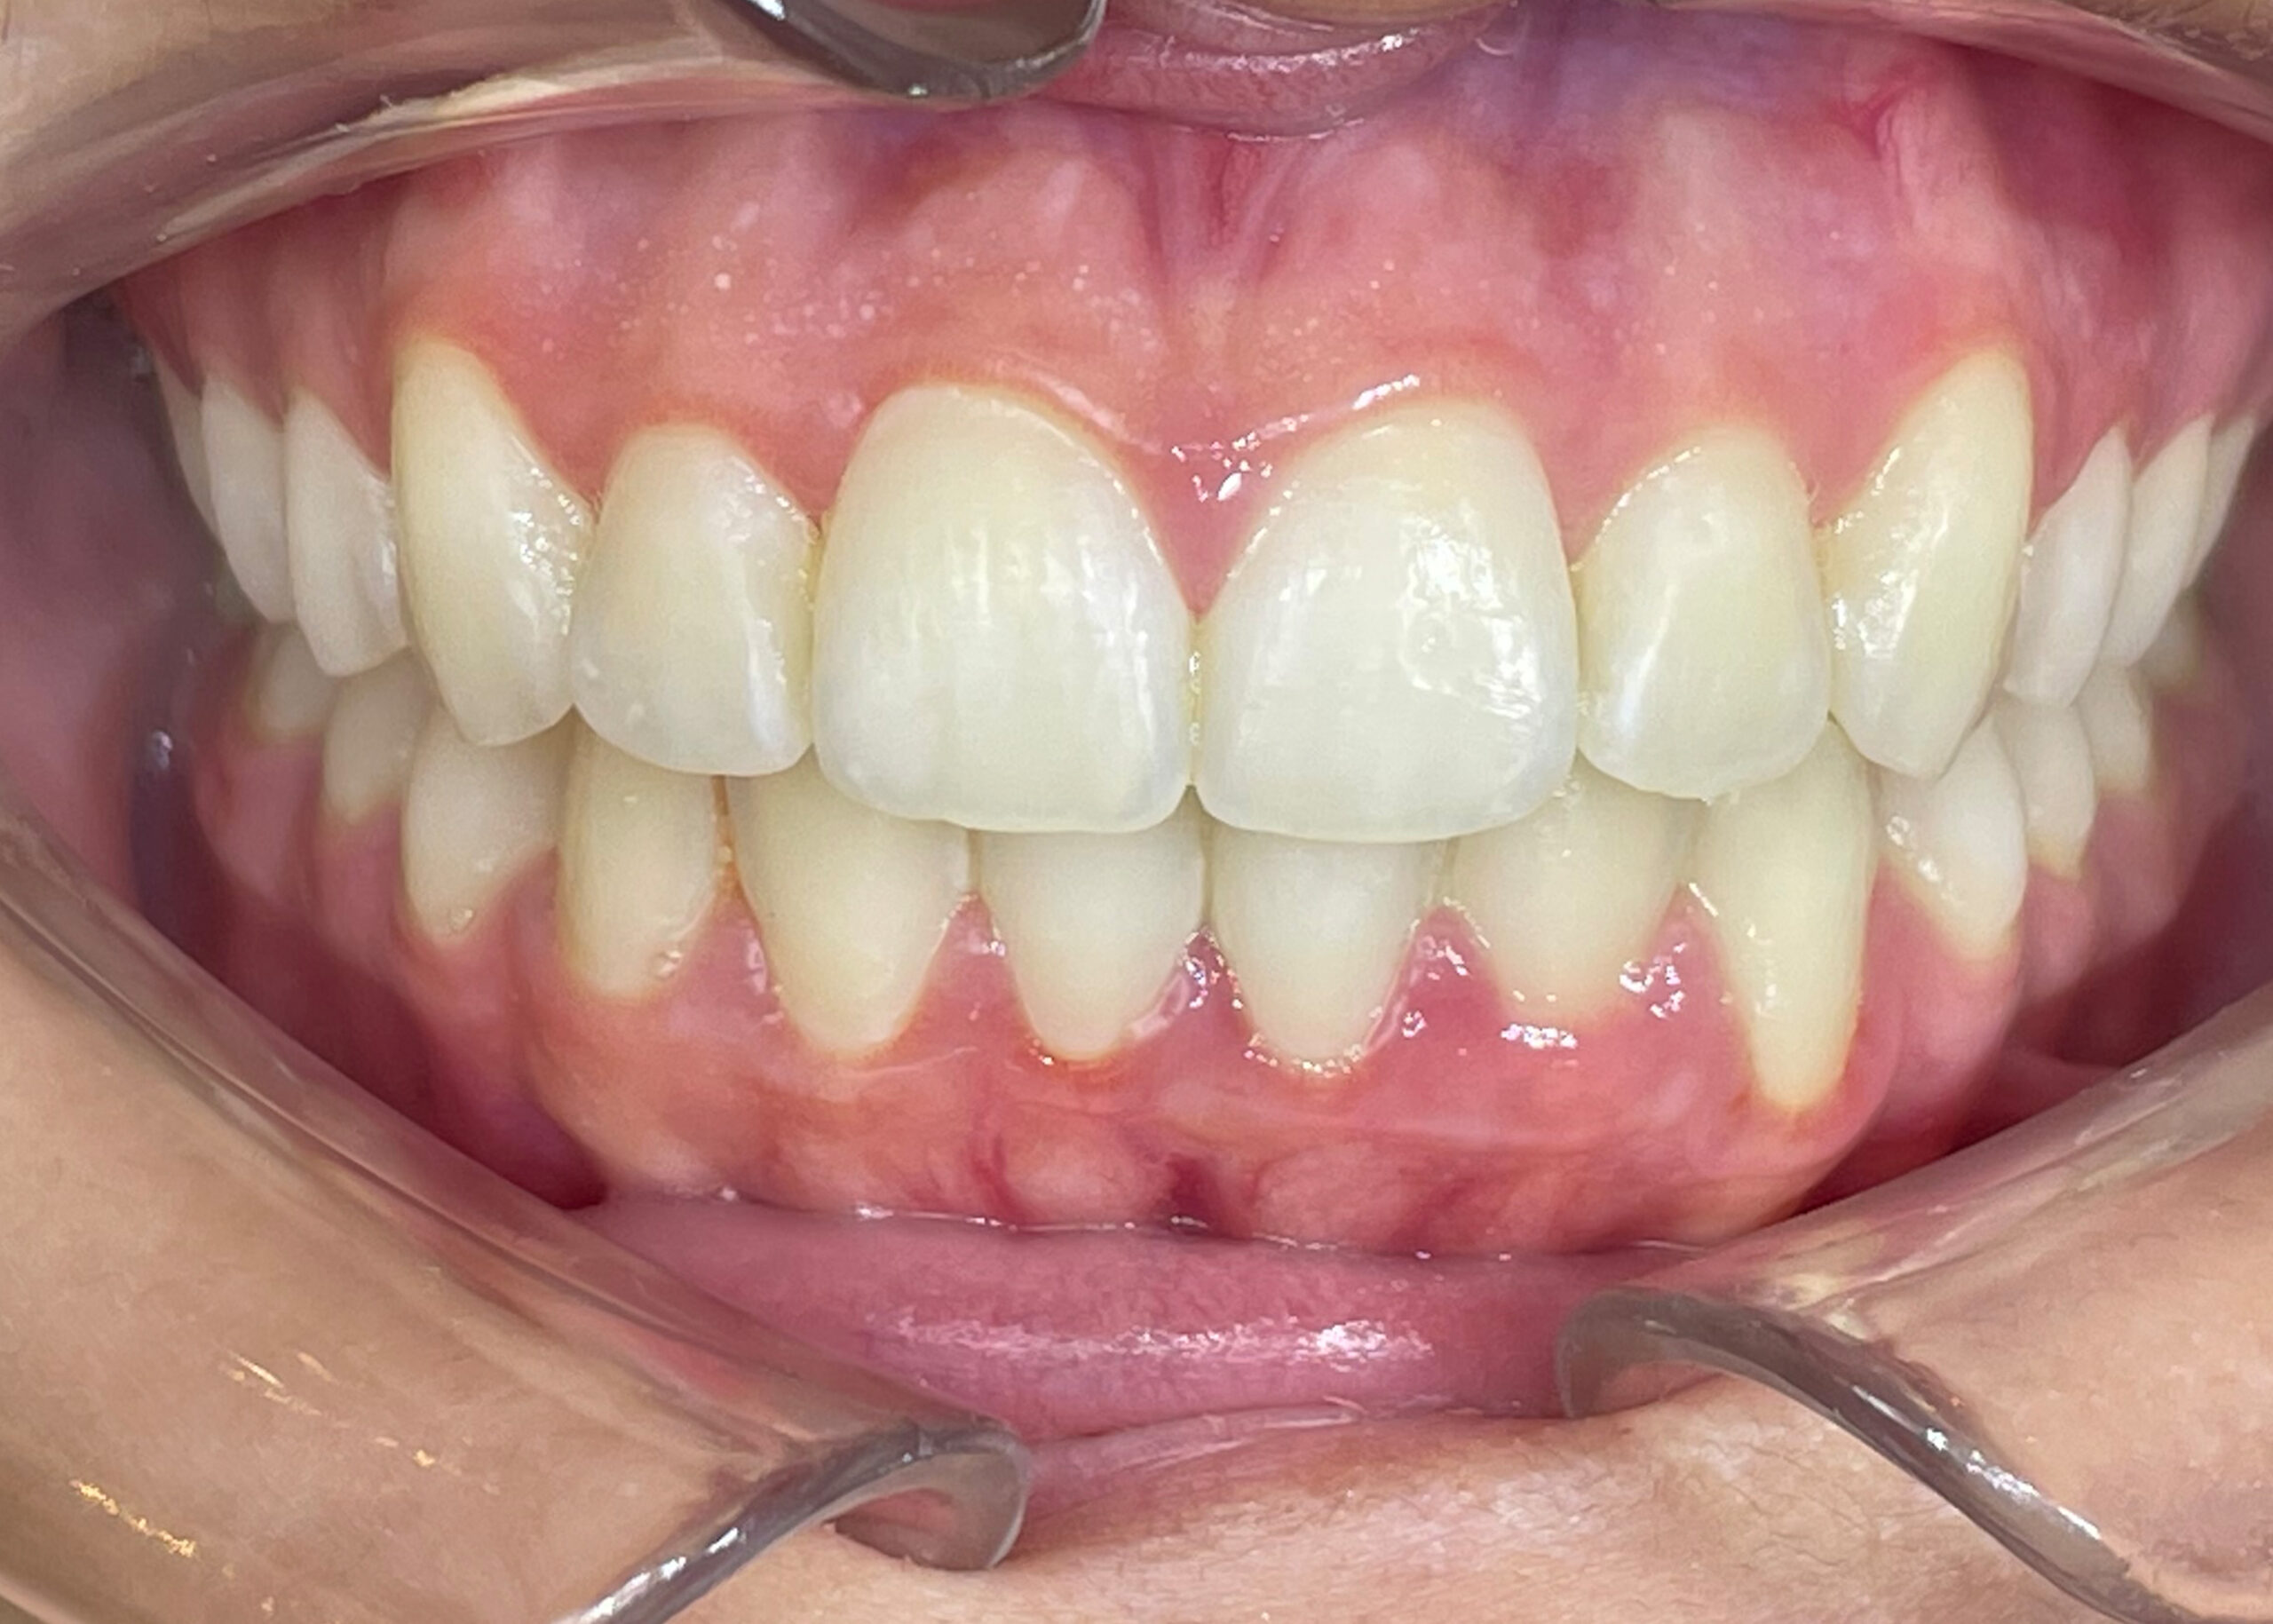

Spark™ treatment of teenager with moderate dento-maxillary discrepancy

This article describes a treatment with Spark Clear Aligners in a 14 year-old patient, with moderate DDM (Dento-Maxillary Disharmony), narrow arches, biproalveoli and hyperdivergence of the bony bases.

At the end of the treatment, which means only 8 months later, the control cephalometric analysis shows an improvement in the incisor axes despite the correction of a moderate DDM.

The Spark Aligners therefore enabled Dr. Pierre Antoine-Dian to obtain a good expansion of the arches, perfect torque control and resolution of the anterior crowding thanks to the protocols used and the predictability of the movements as well as the flexibility provided by Approver Software.